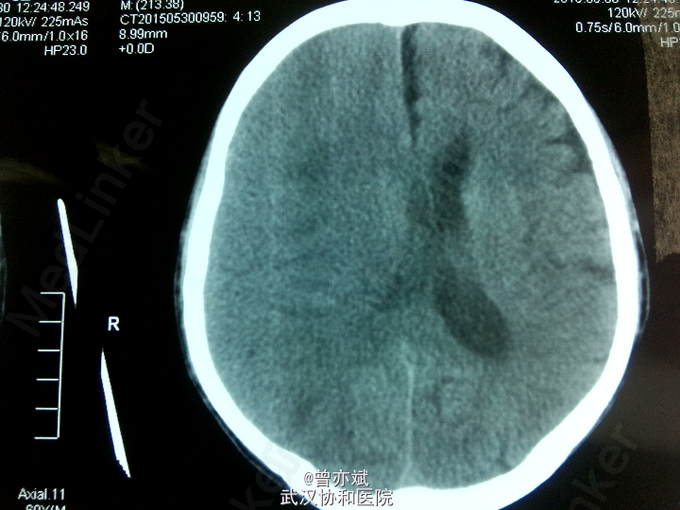

主诉:双下肢乏力3月余,加重1周 现病史:患者2月前意外摔倒后感双下肢乏力,无昏迷、恶心呕吐、头痛头晕等症状,未予特殊处理,今日感双下肢乏力加重,来我院就诊,行CT示右侧慢性硬膜下血肿。

诊断:慢性硬膜下血肿 处理:行微创钻孔引流术